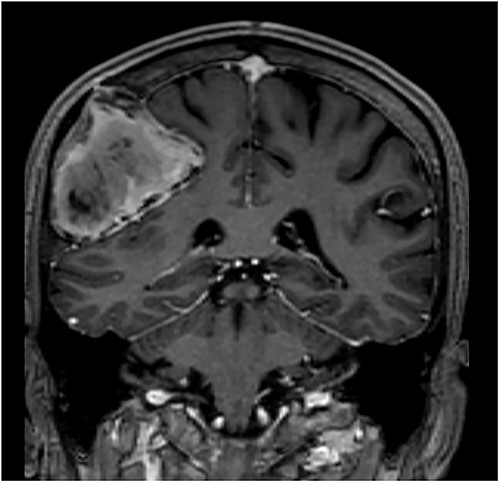

T1-weighted contrast-enhanced coronal MRI scan showing the lesion with intralesional haemorrhagic products. There is no evidence of dural invasion.